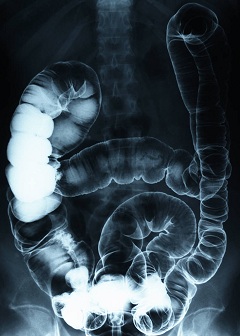

Gutteral view

From all indications, the ACA regarded at least the first colonoscopy at age 50 completely

preventive even if benign or cancerous polyps were removed during the procedure. However, some insurers are viewing the removal of any polyp as a therapeutic action and therefore subject to cost sharing. Yet, a medical director for one insurance company is quoted as saying, “[Polyp removal] is exactly why you’re doing this…if you take that polyp out, you have prevented cancer.” The report went on to mention that this particular insurance company did impose cost-sharing if a specific code was not used by the provider.